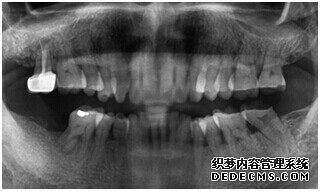

由CT片检查来看,刘女士口腔健康环境还是很好的,牙槽骨也适合种植牙的条件,而且由我们最后一颗牙是非常重要的,经过专家的建议和详细解释了原因之后,刘女士选择了美国百康种植牙。

成功植入种植体后的效果图

种植体成功植入后的CT效果图

整个种植牙完成后的效果图